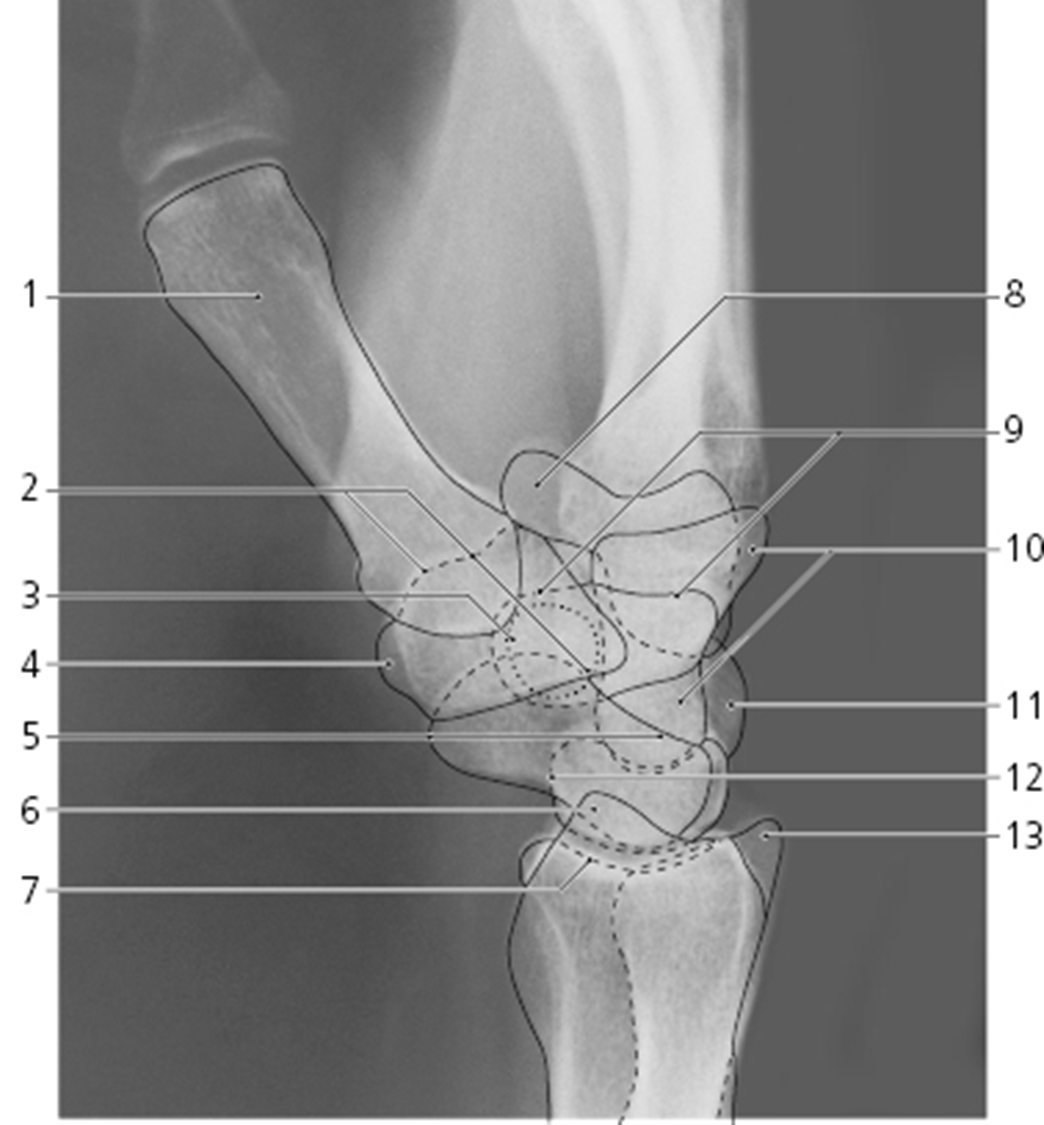

what view is this?

lateral wrist